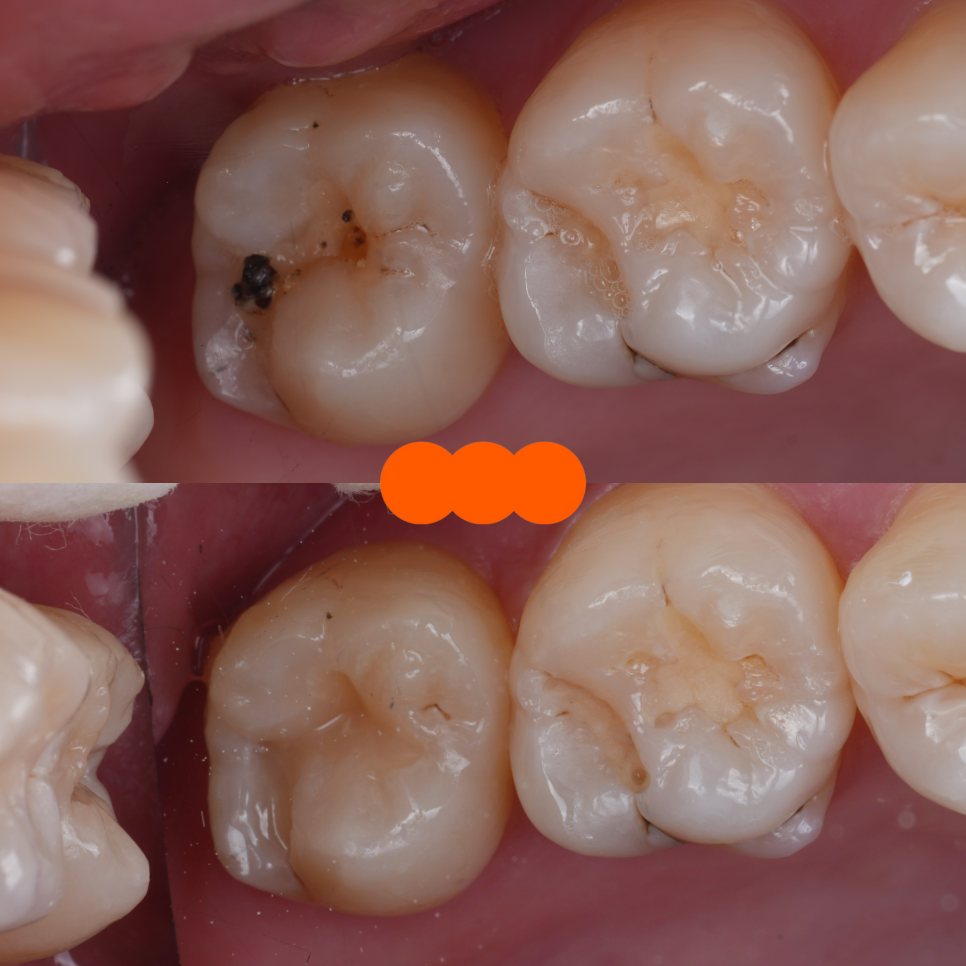

어금니도 충치 제거 후 자연스레 쌓아 올렸어요.

촬영일 : 250909 / 250909

3주 뒤, 환자분께서는 왼쪽 아래 어금니에 치료해둔 레진이 닳아서 진료를 원한다며 내원하셨어요.

촬영일 : 251021

실제로 확인해 보니 예전에 때워뒀던 재료가 변색되고 경계 부분이 떨어지면서 새로 충치가 생긴 곳도 있어서 교체해야 되겠더라고요.

오른쪽 아래 어금니(#37) 하나만 원하셔서 그렇게 해드렸습니다.

큐레이를 이용해 충치만 최소로 삭제하며 진행을 했어요.

#37 완료 / 촬영일 : 251021

그 뒤로 레진을 이용해 말끔하게 채워드렸죠.